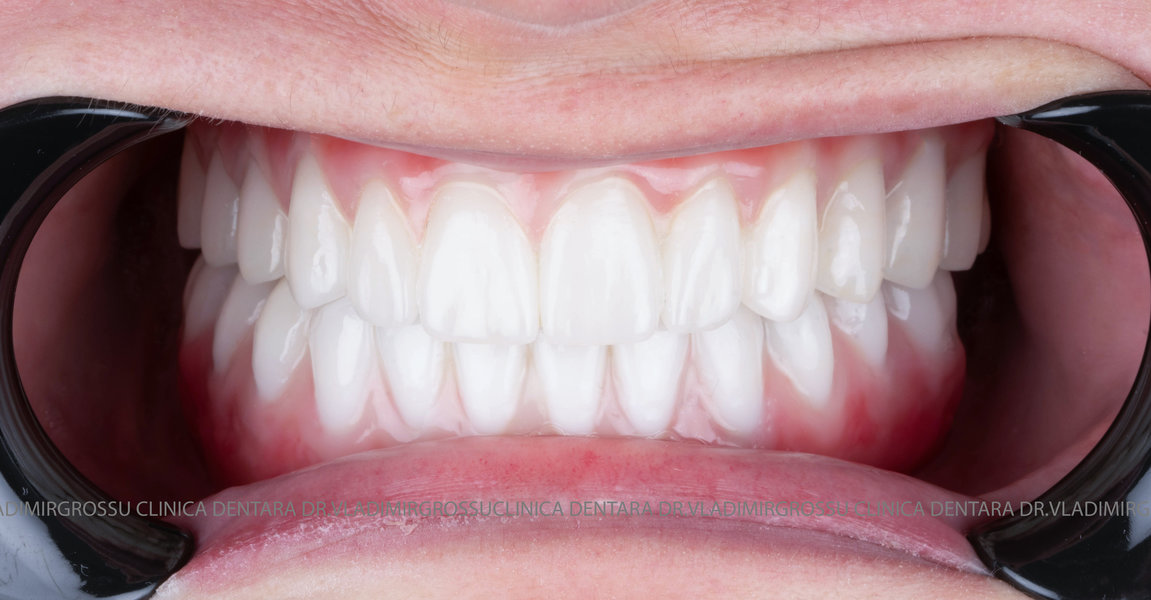

La aproximativ 6 luni de la prima etapă, pacientul revine pentru protezarea definitivă. În această fază, medicul lucrează la nivelul multiunit-urilor și nu direct pe implanturi, ceea ce reduce riscurile pentru implant în etapa protetică.

Pentru proteza definitivă:

- 4 abutment-uri permanente pe multiunit-uri;

- Proteză definitivă din metaloceramică sau zirconiu pe o structură metalică, cu 12 unități (soluția recomandată).